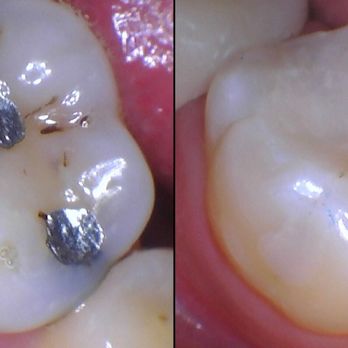

Photos